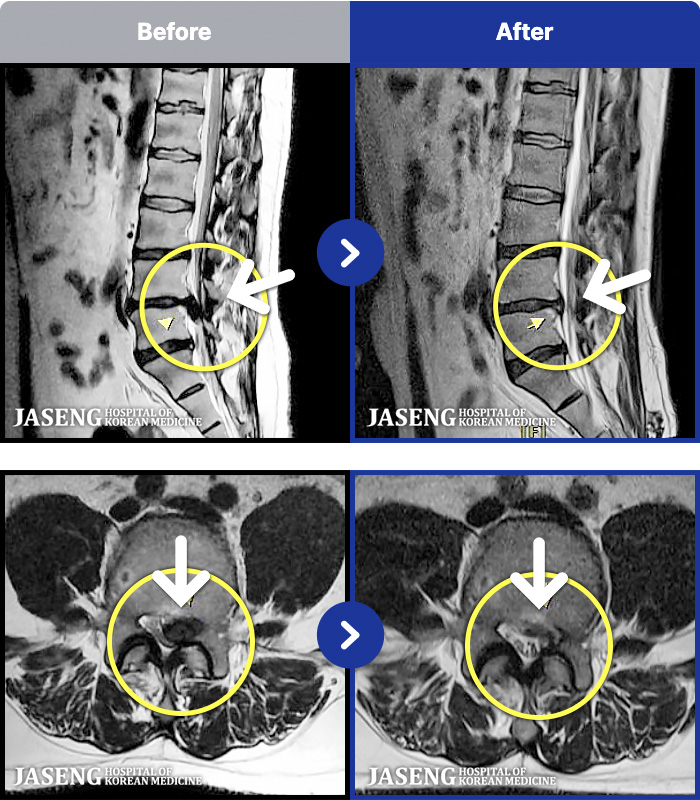

95 MRI ũ ʸ Ȯϼ.

ȯںп Ǹ ǿ ԿǾ, ο ġ ۿ Ƿ ġḦ Ͻñ ٶϴ.